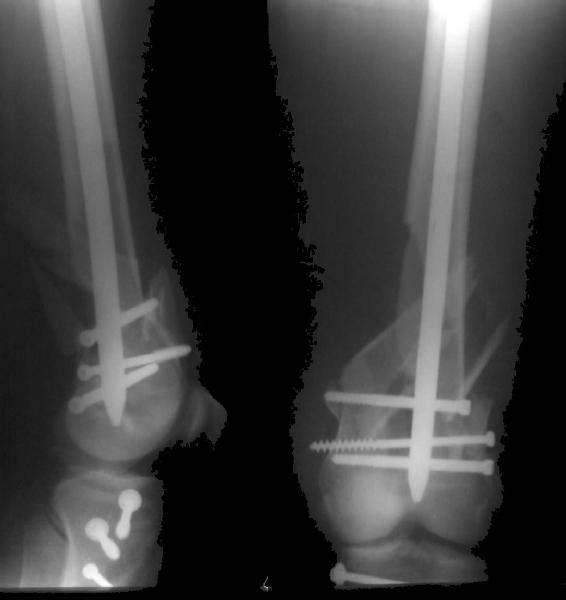

Re: Open supracondylar femur fx

And why LISS is superior here than nail?

Look what we would have done.

Zsolt Balogh 31 Октябрь 2004, 20:46

I would not say that the LISS is superior to the nail. If I would, I had not post original mail. I wanted to generate discussion. Your option is a very viable one. I feel a little bit shaky the distal femur, but it is just gut feeling no science behind it. Any way nice fixation, congarts!

I presented the series at EuroTrauma in May. The "Distal Femur" section of the meeting was very interesting.